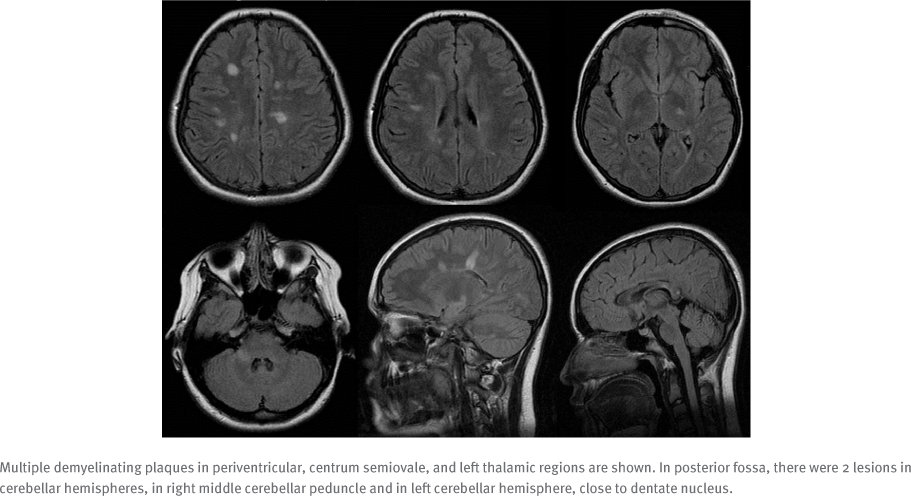

The proband is a 25-year-old woman who received a diagnosis of relapsing-remitting MS at age 13. The diagnosis was based on dissemination in time and space and fulfillment of the McDonald criteria for the diagnosis of pediatric MS. She had multiple attacks involving the sensory, motor, cerebellar, and spinal cord regions. Magnetic resonance imaging (MRI) of the brain and spinal cord demonstrated multiple classical periventricular white matter demyelinating plaques with Dawson fingers and spinal cord involvement (FIGURE 1). She was started on weekly interferon beta (IFNβ)-1a at a dose of 30 μg per intramuscular injection. Unfortunately, her disease progressed both clinically and radiologically for 7 years, despite her adherence with interferon therapy (FIGURE 2). She had 1 to 4 relapses per year, which necessitated treatment escalation for which she was switched to fingolimod 0.5 mg once daily, with good control of her disease during the past 2 years. She has a positive family history of MS in her sister, who is 31 years old and was diagnosed at age 28, as well as her brother, who is 21 years old and was diagnosed at age 17 (FIGURE S1, which is published in the online version of this article at ijmsc.org). Her sister and brother used interferon therapy for 1 and 2 years, respectively, with multiple relapses and deterioration of Expanded Disability Status Scale scores and gait. They were shifted to fingolimod 0.5 mg once daily, with excellent response and improvement in Expanded Disability Status Scale scores. Their brain MRIs showed classical multiple periventricular demyelinating lesions, and they did not have cerebellar atrophy. The parents were not consanguineous, and none of the siblings had genetic diseases that run in the family, including cystic fibrosis, glucose-6-phosphate dehydrogenase deficiency, familial Mediterranean fever, or any other genetic diseases.

Magnetic Resonance Image of the Brain, Fluid-Attenuated Inversion Recovery Sequencing, at Age 14